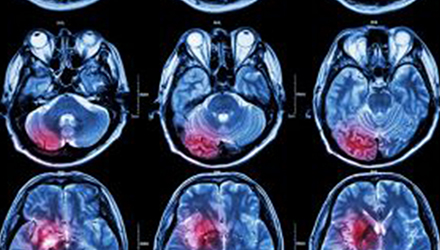

在這項研究中,研究人員使用功能核磁共振成像(fMRI)觀察大腦中血液含氧量的變化。研究人員首先研究了耳鳴患者和無耳鳴者的大腦活動,其目的是比較兩組受試者大腦處理情緒的方式。

在功能磁共振成像檢查中,受試者分別聽30種“愉悅”的聲音、30種“不愉快”的聲音和30種“中性”的聲音。這些聲音包括小孩咯咯笑,嬰兒啼哭,以及熱水壺?zé)_的聲音。

功能磁共振成像的結(jié)果顯示,當(dāng)暴露于情緒性聲音下,耳鳴患者大腦不同區(qū)域的活動比沒有耳鳴者的活動更強烈。接著,研究人員進行了更深入的研究:耳鳴患者的大腦活躍性和耳鳴嚴(yán)重程度的關(guān)系。

調(diào)查結(jié)束后,再進行功能核磁共振成像檢查。第二輪功能核磁共振成像顯示,那些耳鳴較輕的患者實際上使用了大腦不同的區(qū)域來處理情緒信息。

傳統(tǒng)觀點認為,大腦中的扁桃體是處理情緒的關(guān)鍵,但此次研究發(fā)現(xiàn),那些不被耳鳴困擾的患者實際上使用更多大腦額葉來處理情緒。這類患者額葉活動更顯著的原因是,額葉通常更多地用于注意力、計劃和沖動的控制。